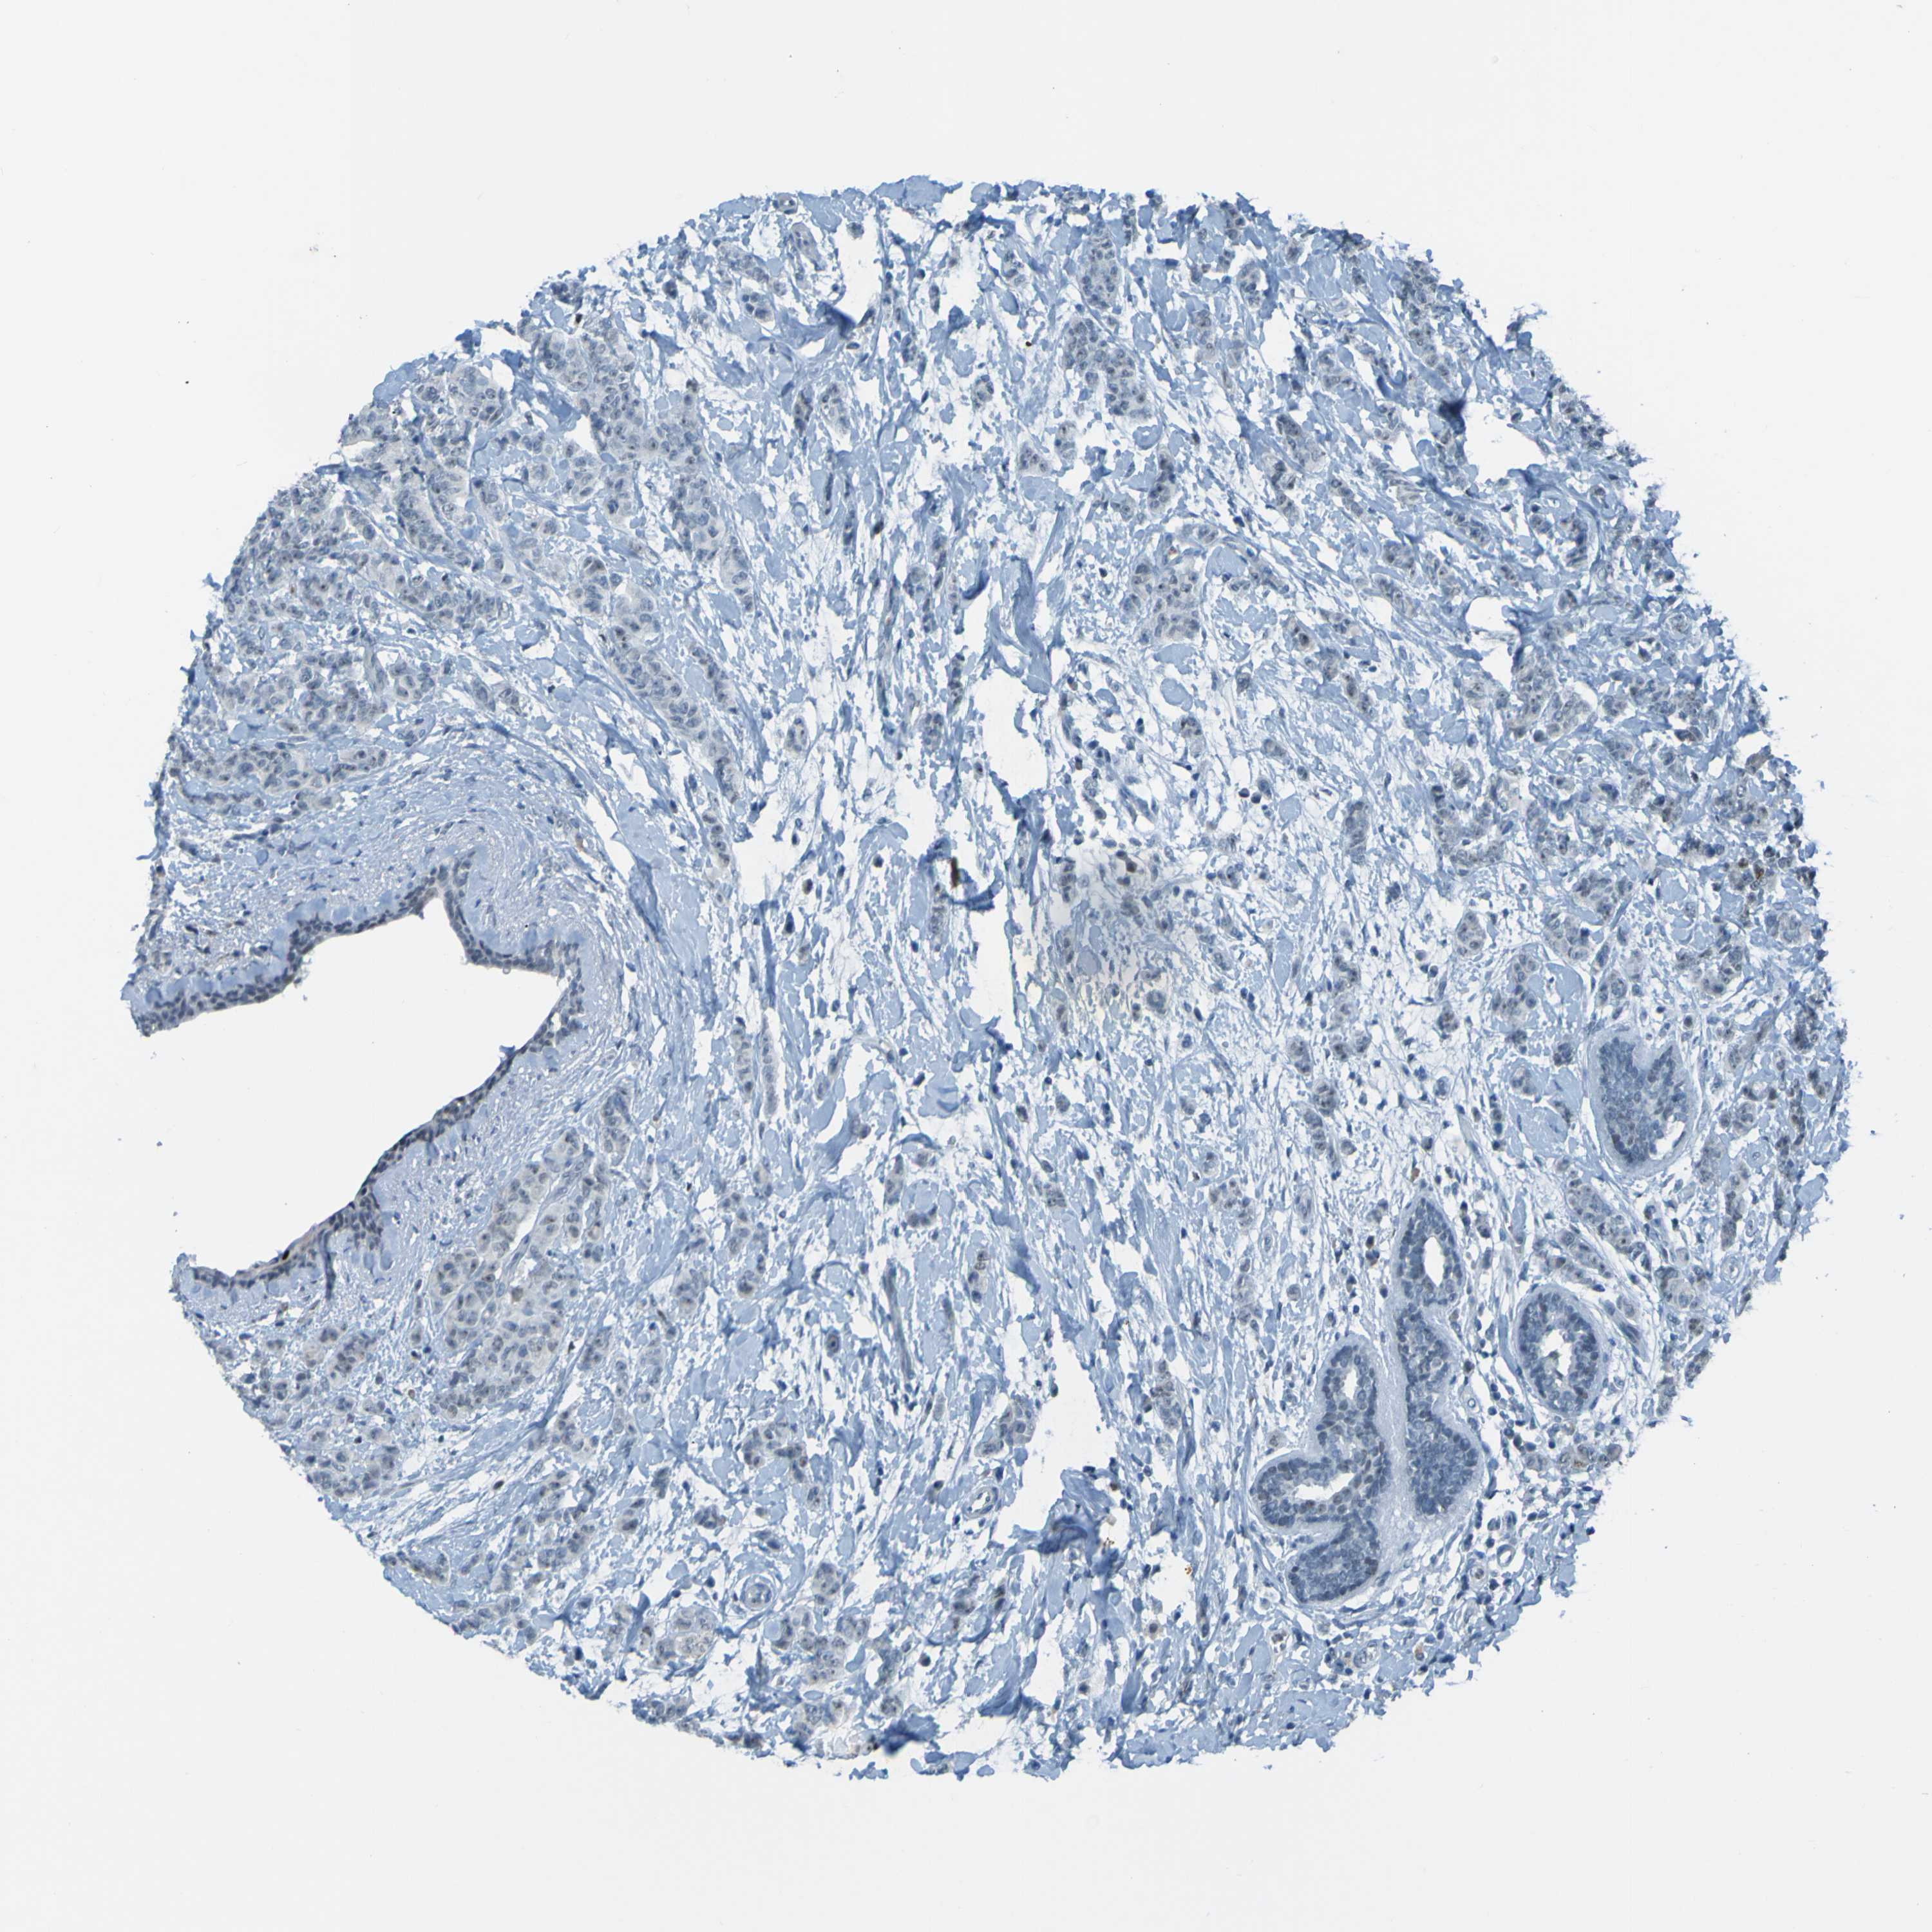

CANCER BREAST CANCER Show tissue menu

BRCA TCGA BRCA VALIDATION PROTEIN EXPRESSION

Breast cancer

Human cancer